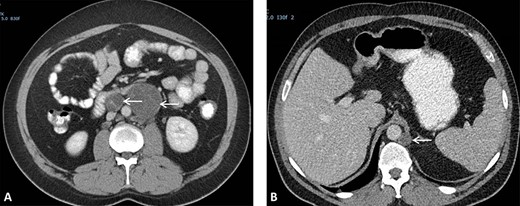

(A) CT scan showing two retroperitoneal masses. (B) CT scan showing retroperitoneal recurrence..

He presented himself 6 years later with a request to resume follow-up, in the absence of symptoms. A retroperitoneal recurrence located at the left retrocrural space with a diameter of 17 mm (Fig. 2B) with normal tumor markers was diagnosed 87 months after initial resection of RRTM. The recurrence, suggestive for a growing teratoma, was located far from the previous operative resection area. The patient was discussed in the multidisciplinary tumor board and offered a posterior retroperitoneoscopic resection of the recurrent disease with the highest chance of a complete resection of this late relapse without surgically dealing with scarred tissues and adhesions caused by a former operation field.